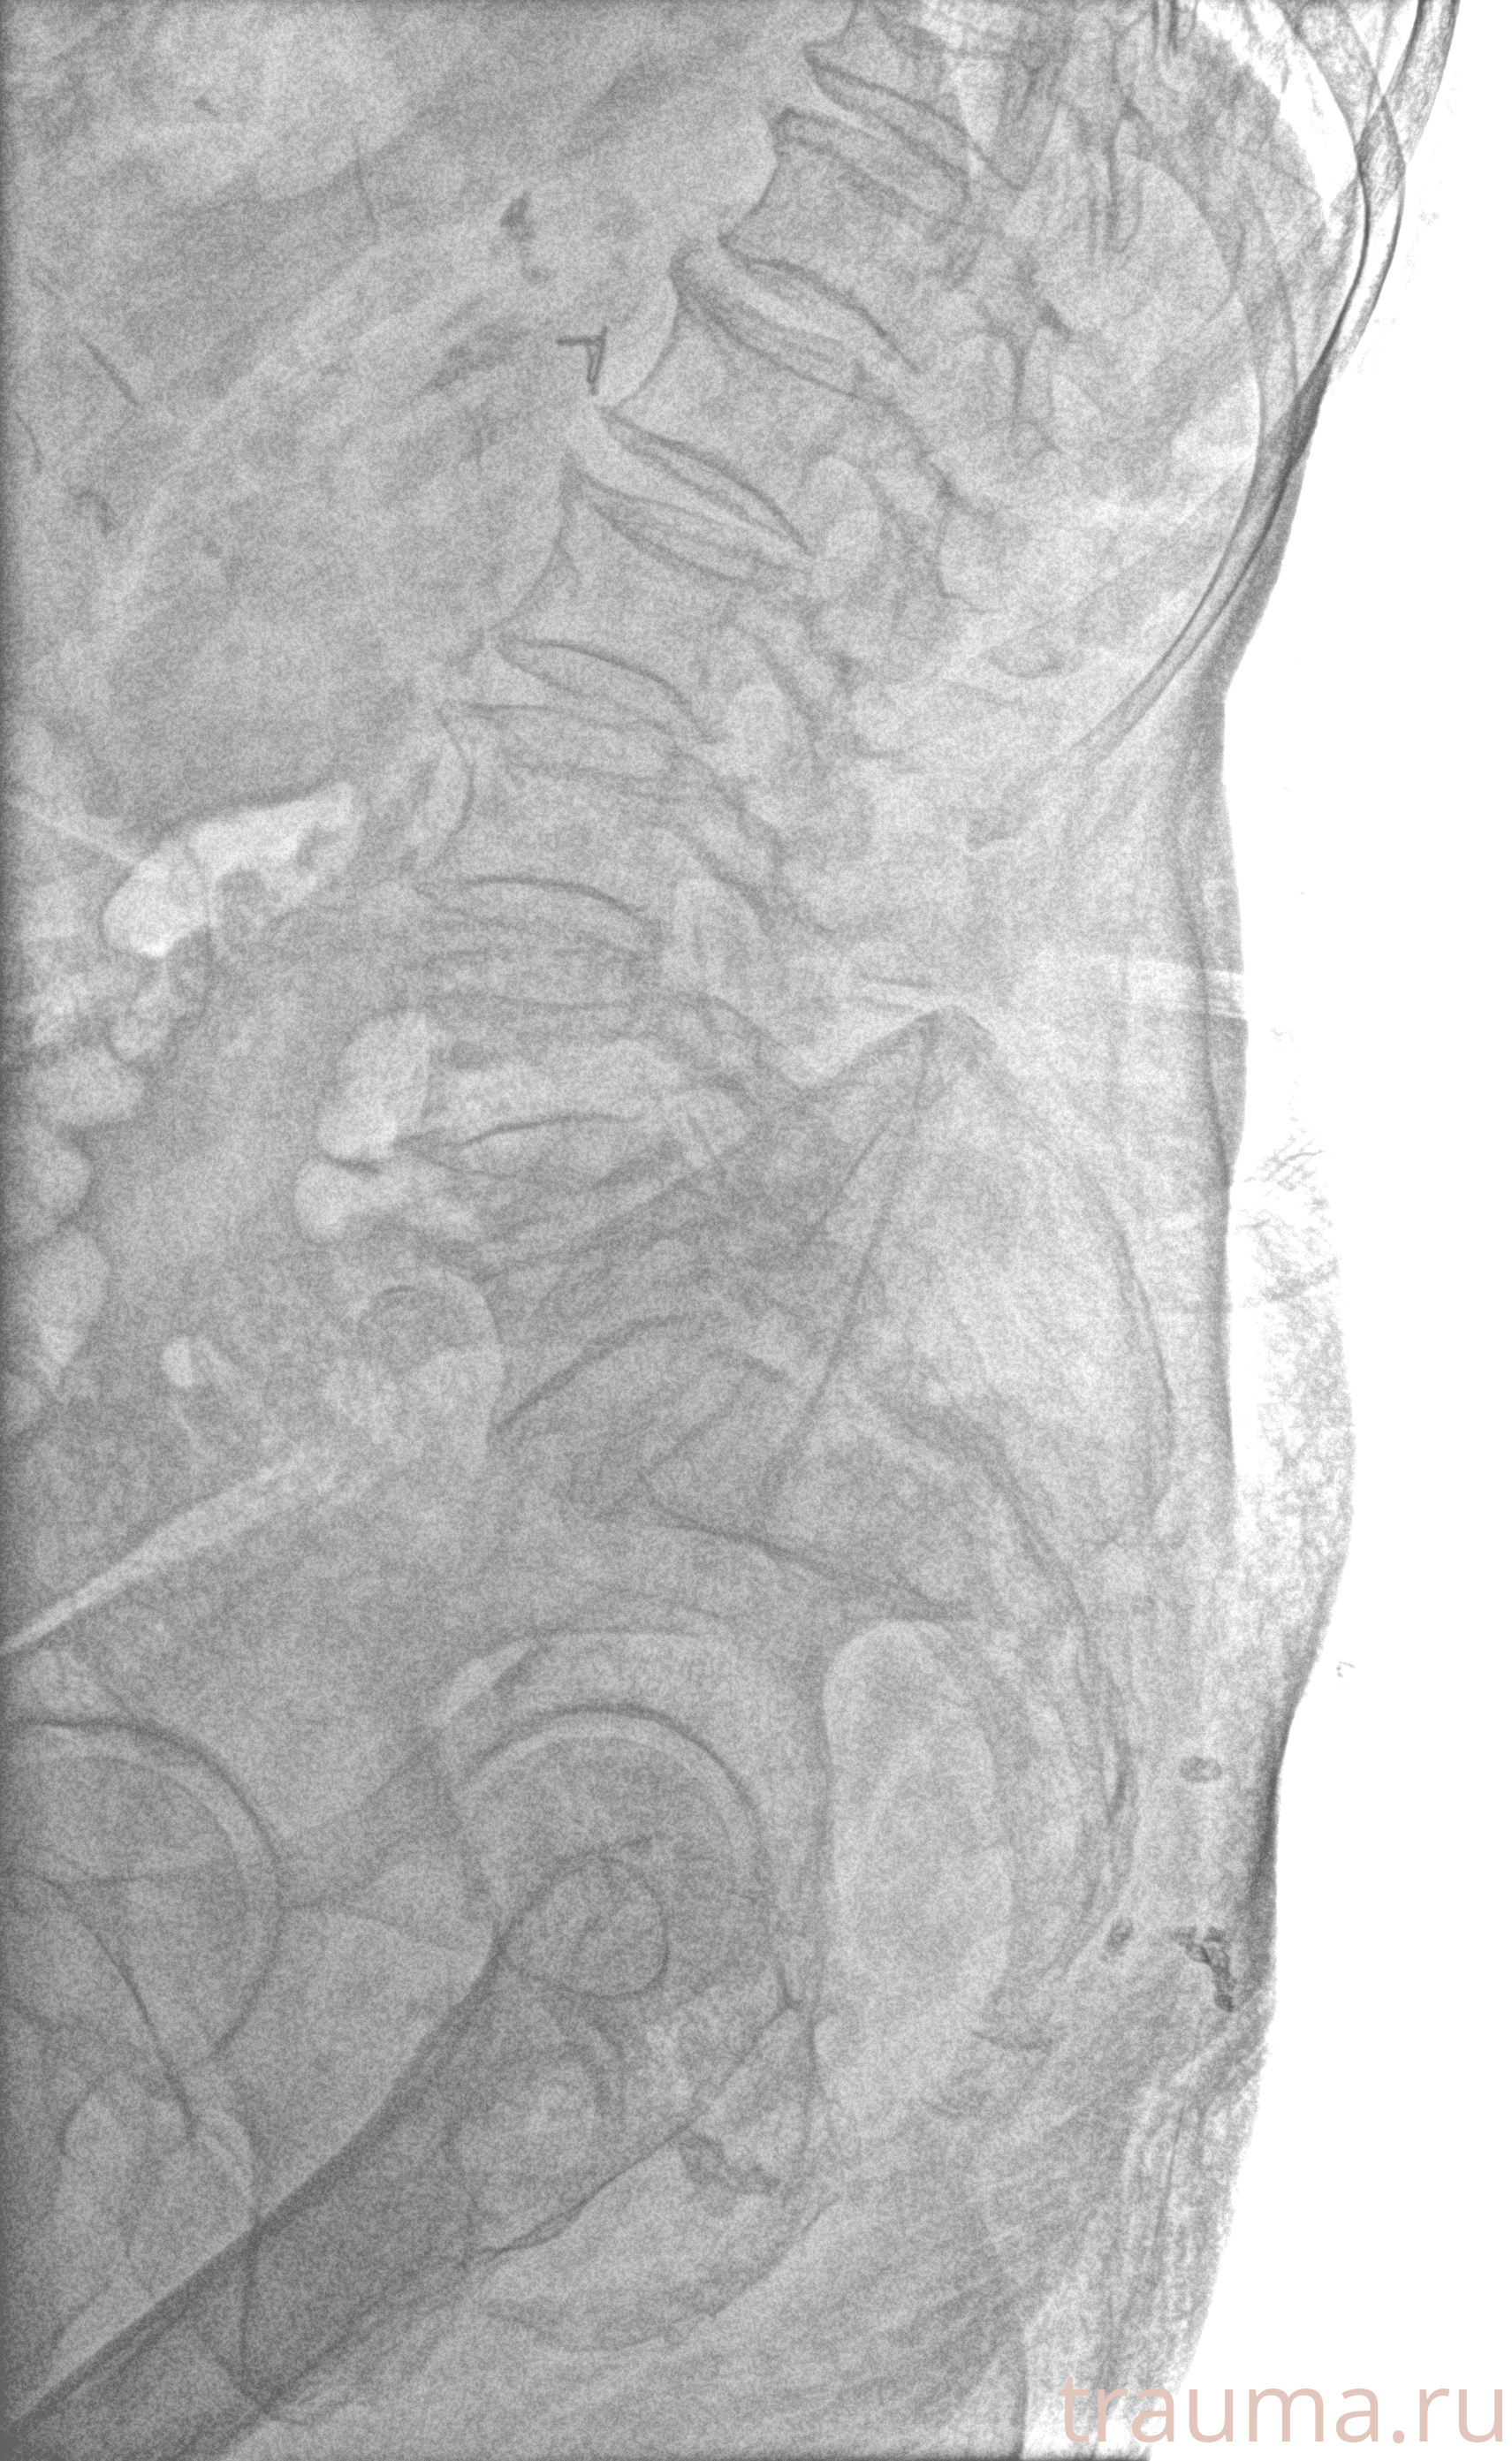

Рентген на дому: по вашему адресу приезжает врач-рентгенолог, травматолог-ортопед с мобильным рентгеновским аппаратом, проводит диагностику травмы или заболевания, делает необходимые рентгенограммы, дает рекомендации по дальнейшему лечению. Получить качественные снимки в домашних условиях возможно благодаря уникальной методике, разработанной МосРентген Центром для института  Склифосовского